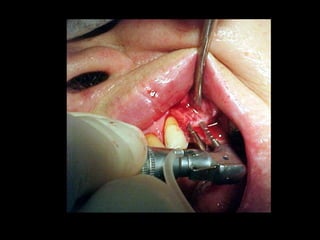

Reimplante ortodóncico

Receptor

Receptor momento de trasplante

Trasplante 3 meses de evolución